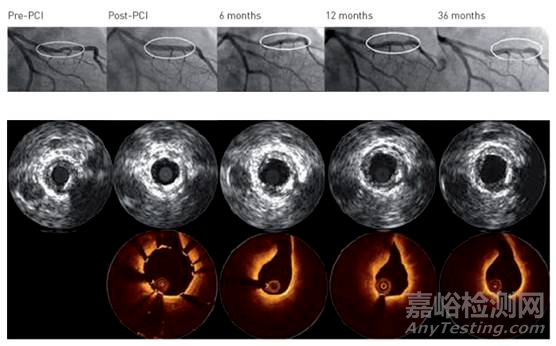

BIOMAG-I 研究標志著第三代藥物洗脫可吸收鎂支架(DREAMS 3G)在人類體內的首次臨床應用評估,這是一項具有里程碑意義的探索。本研究旨在通過高精度的影像學手段——光學相干斷層掃描(OCT)與血管內超聲(IVUS),在經(jīng)皮冠狀動脈介入治療(PCI)后的6個月及12個月時間點上,系統(tǒng)性地評估血管愈合的多個關鍵參數(shù)。

具體而言,研究聚焦于支架的體內降解過程及其對血管結構的影響,重點關注支架的可見性變化、血管壁與支架覆蓋區(qū)域的相互作用,以及新生內膜(即血管內壁為修復損傷而新生的組織層)的生長模式與動態(tài)變化。

在12個月的OCT復查中,令人鼓舞的是,超過99%的鎂支架已完全降解至肉眼不可見,且未觀察到支架網(wǎng)梁貼壁不良的情況,這表明DREAMS 3G支架在體內的生物相容性和降解性能優(yōu)異,有效避免了傳統(tǒng)永久性支架可能帶來的長期異物反應。

盡管血管總面積在觀察期間未發(fā)生顯著變化,但值得注意的是,從PCI術后至6個月時,最小管腔面積(MLA)出現(xiàn)了顯著的生理性縮小(從6.88 mm²減少至4.75 mm²,p<0.0001),這反映了血管在愈合過程中的自然重構現(xiàn)象。然而,至12個月時,MLA未再進一步顯著減小,提示血管結構已趨于穩(wěn)定,未發(fā)生不良的重塑。

研究還揭示了可吸收鎂支架植入后新生內膜生長的獨特模式。在12個月時,高達89.3%的患者中觀察到了明顯的新生內膜突出,這是血管愈合過程的一個重要標志。然而,從6個月到12個月,新生內膜的平均面積卻減少了47.4%,這可能反映了新生內膜在成熟過程中的重塑與優(yōu)化,即從初期的過度增生逐漸轉變?yōu)楦鼮榉€(wěn)定、功能性的內膜結構。